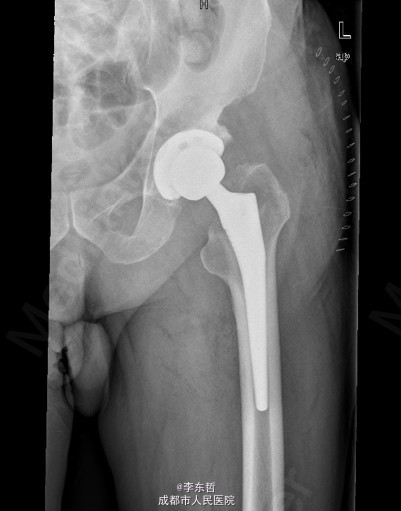

初步诊断:左髋创伤性骨关节炎 诊疗计划:1、向患者及家属交待病情及注意事项。2、向上级医生汇报患者病情。3、完善血常规,心电图,肝肾功等检查,择期手术治疗。4、密切观察病情变化,根据病情及时处理。

随访无特殊